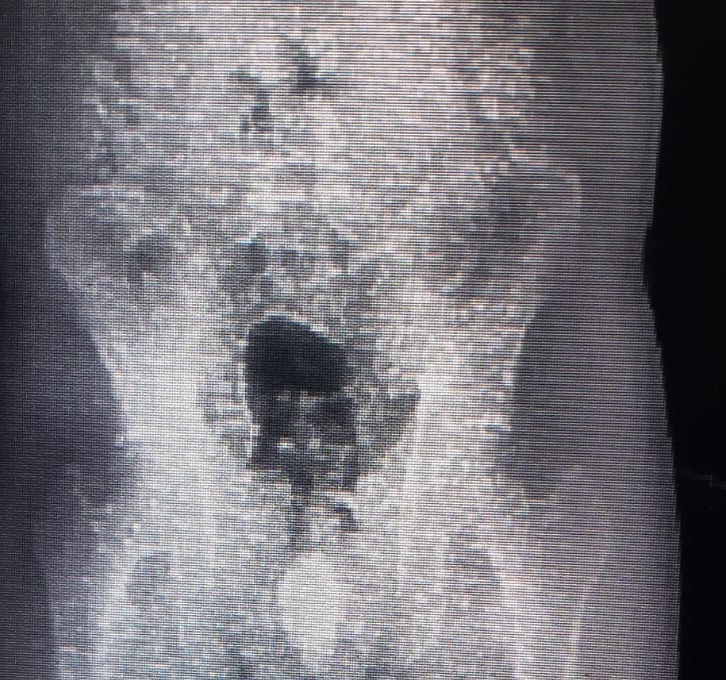

• Um preso levado pela Polícia Federal foi identificado com entorpecentes no estômago, durante entrada na Penitenciária de Regime Fechado da Gameleira II, na tarde do dia 1º de outubro. Os policiais penais identificaram os entorpecentes no interior do corpo de um preso boliviano durante revista com escâner de corpo, procedimento de praxe no presídio quando do ingresso de novos internos.

Conforme informação dos policiais penais, ao ser identificado na imagem, o novo detento foi questionado se havia engolido ou introduzido algum ilícito em seu corpo, quando confessou ter engolido nove cápsulas contendo cocaína, três dias antes.

O homem foi isolado em cela de espera e, algumas horas depois, expeliu os entorpecentes conforme havia confessado. Foi novamente vistoriado com o escâner, mas nada foi identificado.